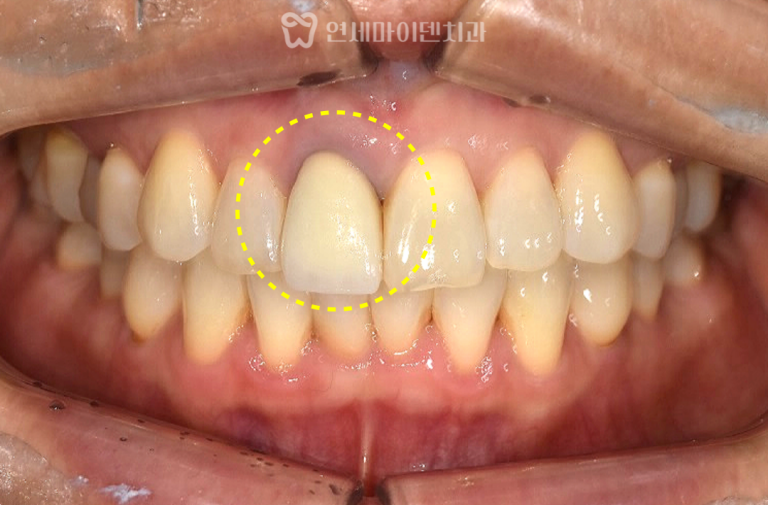

육안으로 보기에도 잇몸 염증이 심한 상태였습니다.

잇몸 염증은 치아의 뿌리 끝이 아닌

치아 중간 부위에서 심하게 발생해 있었고,

이런 형태의 염증은 치근단염보다

예후가 좋지 않은 경우가 많습니다.